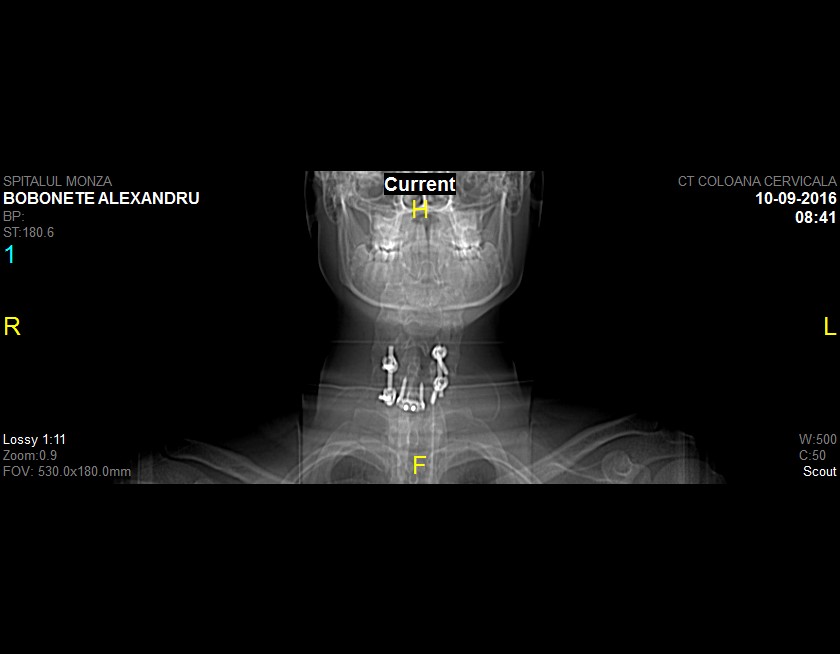

Povestea spusă de mama lui Alexandru (17 ani) Era o zi de vară ca oricare alta – 12 iunie 2016. Alex pleca la antrenament – este pasionat de fotbal și joacă de la 7 ani – noi (eu și tatăl lui) plecam la serviciu. Ziua a decurs normal, până când am primit un telefon de […]